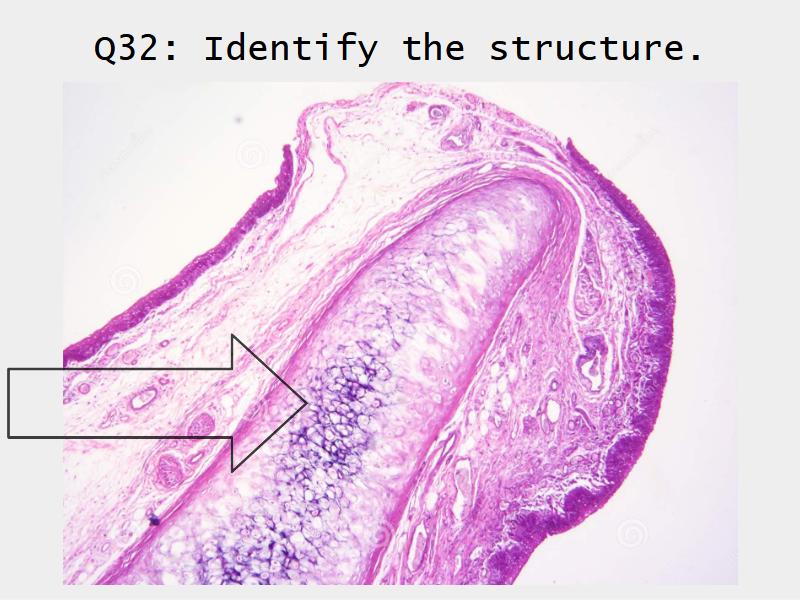

- Slide 71: Nostril

Nostril